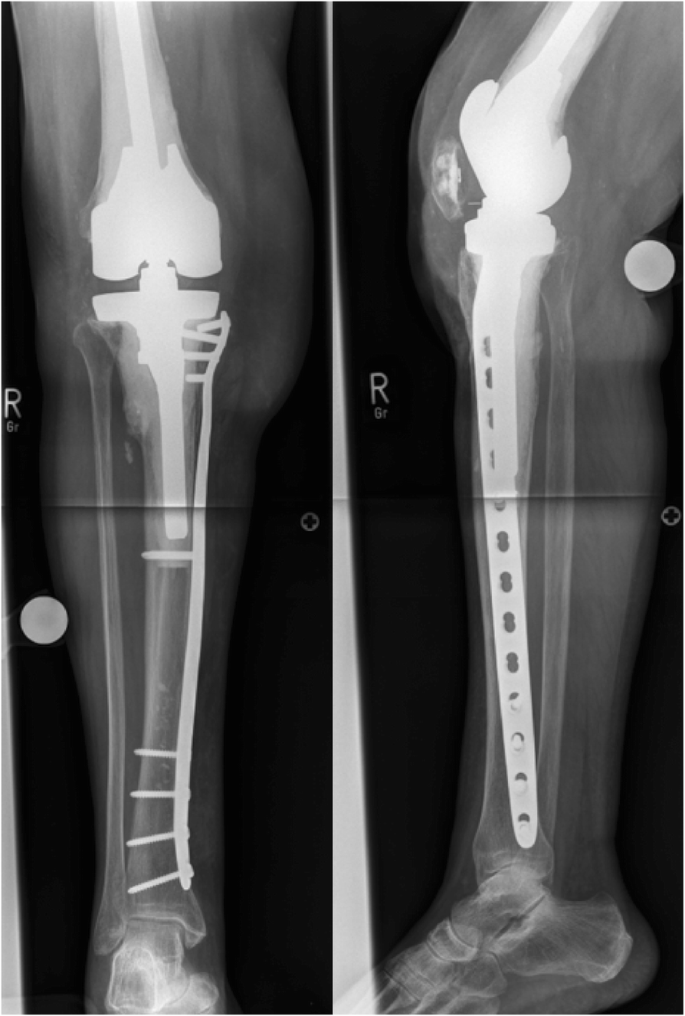

Datei Osteolyse Nach Huft Tep Jpg Wikipedia